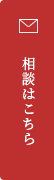

治療前1

出っ歯舌側矯正

上下舌側矯正を希望。

通院状況や歯みがきの協力が良かったため、1年7ヶ月で治療を終えることができました。※装置と注意事項に関しては、大人の矯正装置一覧へ。

- 年齢:20歳女性

- 主訴:出っ歯が気になる

- 基本矯正料金:120万円

- 治療期間:1年7ヶ月

- 抜歯部位:上顎両側第一小臼歯